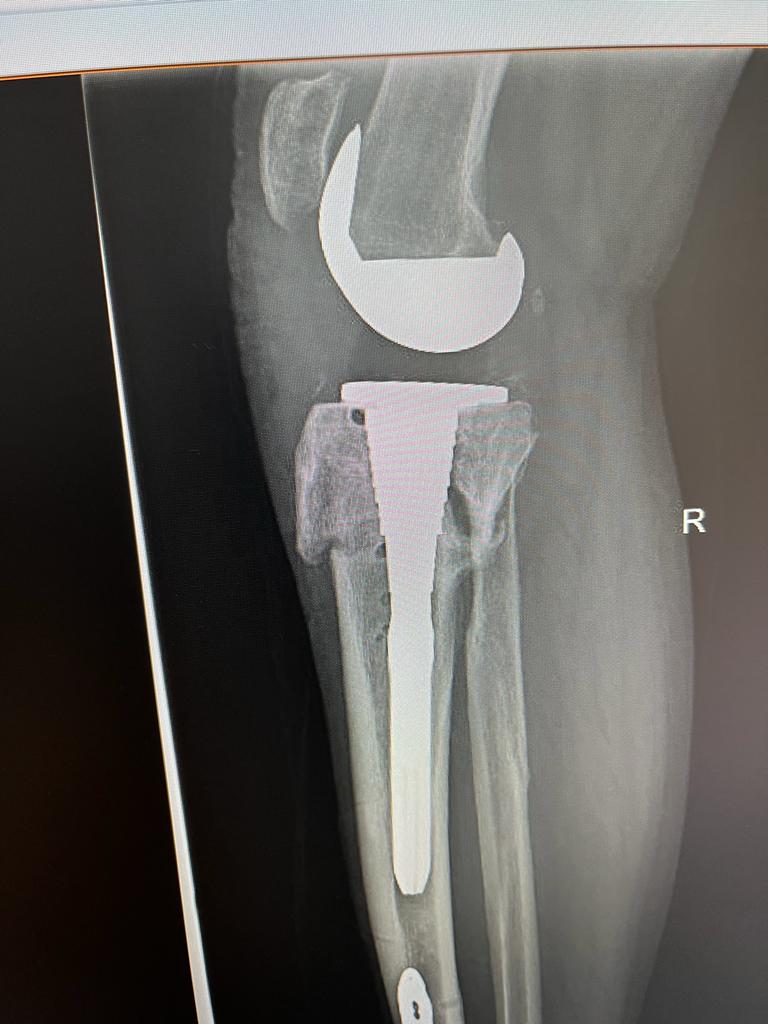

In cadrul sectiei de ORTOPEDIE – TRAUMATOLOGIE, s-a realizat cu succes o interventie chirurgicala cu grad ridicat de dificultate, la un pacient in varsta de 53 ani, care a suferit în urma cu aproximativ opt luni o fractura cominutiva bituberozitara de platou tibial cu intarziere în consolidare vicioasa.

In cele opt luni, genunchiul pacientului s-a deformat progresiv, materialul de osteosinteza a migrat generand dureri continue pacientului iar mersul fiind posibil doar cu cadru.

In acest context, deformarea severa a tibiei si calitatea slaba a calusului osos impuneau o interventie chirurgicala de protezare a genunchiului cu endoproteza de revizie. Aceasta a fost efectuata de catre echipa medicala condusa de dr. CHIREA MARIUS, medic primar ORTOPEDIE-TRAUMATOLOGIE.

„Tinand cont de varsta tanara a pacientului,  am optat la o versiune necimentata a endoprotezei și augmentarea la nivelul tibiei proximale (unde prezenta intarziere in consolidare si stoc osos precar) cu un con metalic Porocoat  pentru a facilita si stimula osteoinductia. De asemenea, femurul si tija centromedulara tibiala care preia tensiunile din genunchi sunt necimentata. Acest dispozitiv protetic ne-a fost adus special pentru acest caz de firma Johnson and Johnson careia ii mulțumim. Totodata multumim si echipei operatorii și colegilor anesteziști”.

Rezultatul postoperator a fost un succes, s-a reusit alinierea genunchiului, dr. CHIREA MARIUS, medic primar ORTOPEDIE-TRAUMATOLOGIE obtinand o proteza necimentat primara stabila si cu mobilitate maxima.